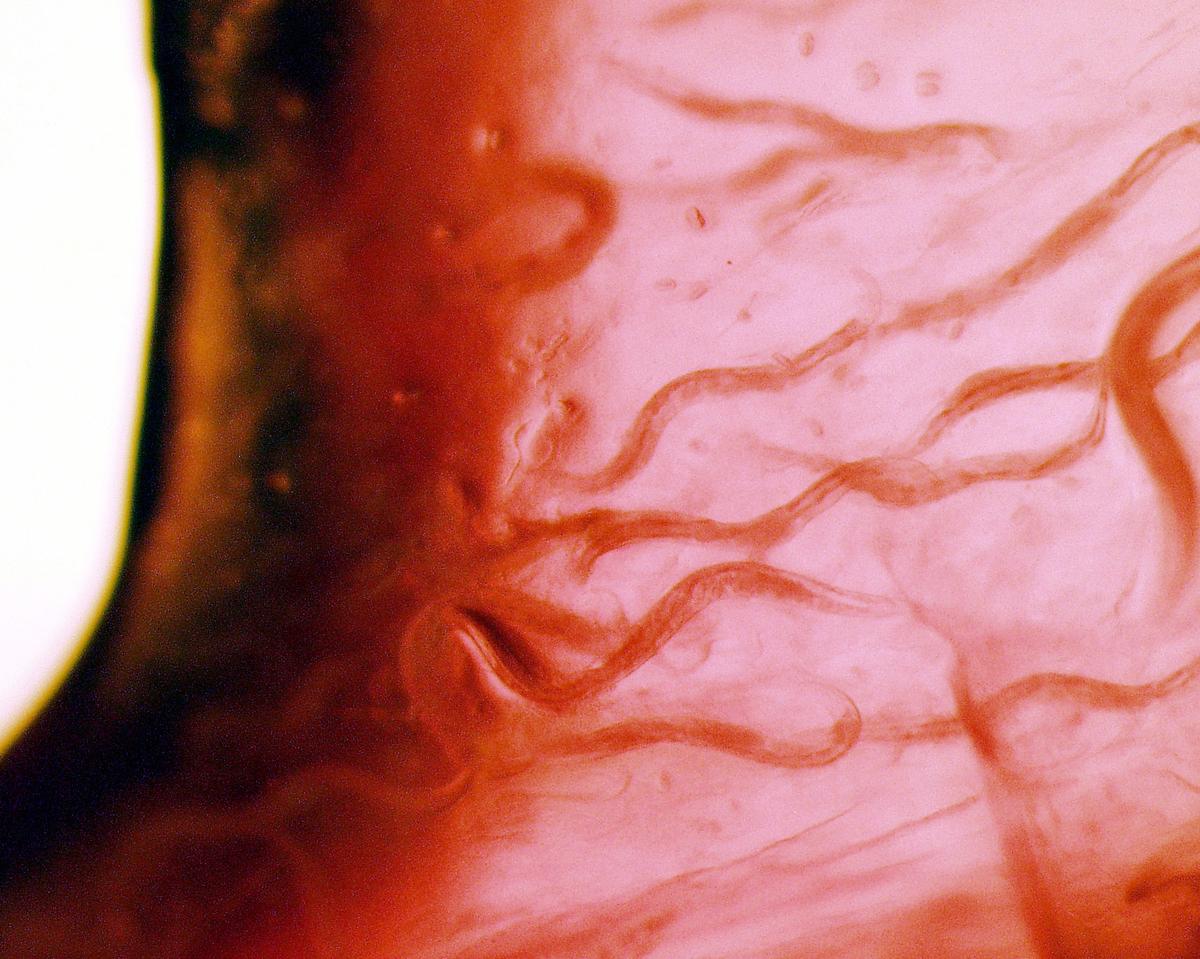

It is estimated that up to 90 percent of us will have a problem with parasites at some point in our lives. While living off the human body, these little critters can cause a variety of acute and chronic illnesses, and all too often, we don’t realize they are the cause.

Whether it is lice, mites, ticks, fleas, worms, or microscopic protozoa, parasites are extremely difficult and often impossible to notice. This makes them especially dangerous as they lurk unseen, waiting to take up residence in our bodies, primarily through the following four ways.